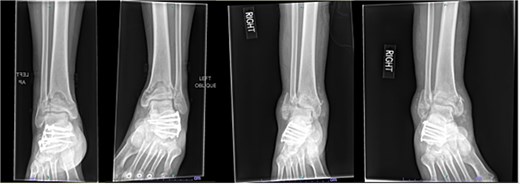

One year after the initial surgery, the left leg healed without any complications. However, the right leg developed nonunion through the distal tibia, along with posttraumatic arthritis. As a result, the patient underwent a right ankle fusion. Additionally, 2.5 years after the index surgery (1.5 years after the ankle fusion), the patient required removal of the right lateral fibular plate due to painful hardware. Six months later (3 years post-index surgery), the patient then underwent subtalar fusion due to post-traumatic arthropathy and ongoing pain (Fig. 2).

Radiographs of patient 1 obtained 3 years after the index procedure, including AP view of the left ankle and lateral and oblique views of the right ankle following subtalar fusion.